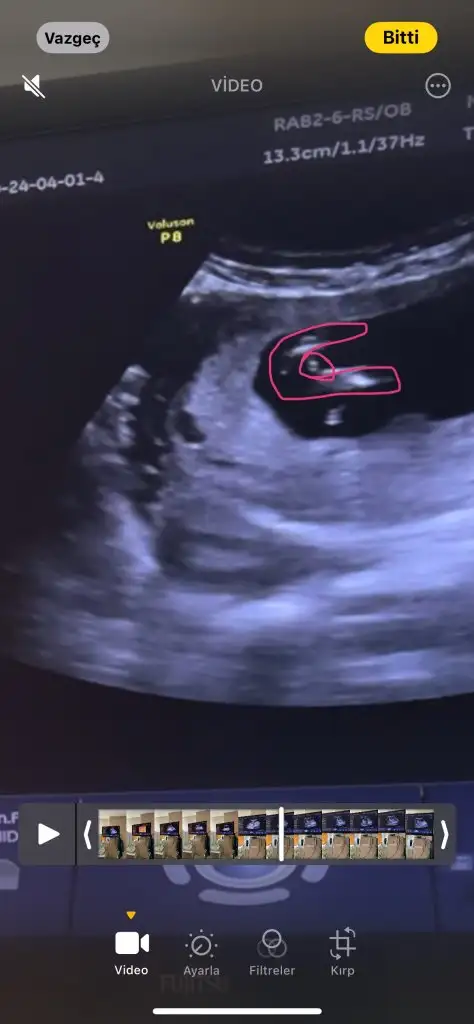

Kızlar bugün dayanamayıp başka bir doktora gittim, dr bacak arasını gösterdi. Videoya çekmiştik, bu görüntüleri videodan çektim. Erkek dedi, erkek bebek bekleyenler sizin de böyle mi acaba?🙈

Renkli kan akımına baktı mı? Kordon falan değilse erkeğe benzettim ben de.